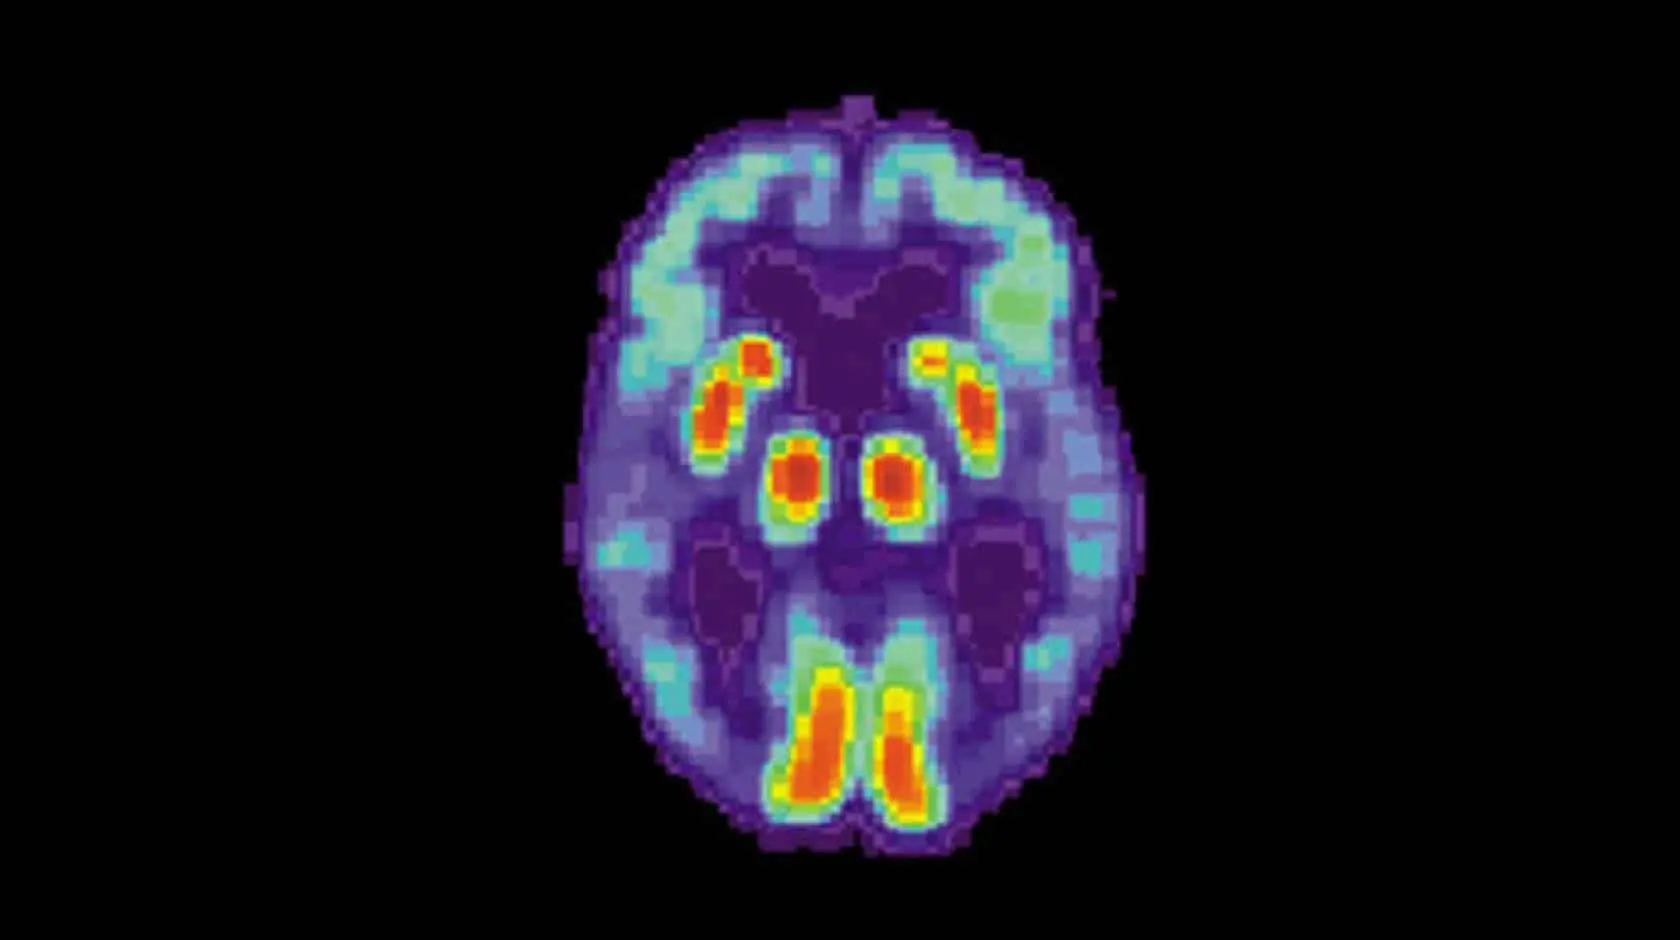

Данные Всемирной организации здравоохранения свидетельствуют: в 2021 году более 57 миллионов человек жили с деменцией. Глобально ежегодно фиксируется почти 10 миллионов новых случаев. Среди форм слабоумия лидирует болезнь Альцгеймера, поражающая преимущественно людей старше 65 лет и прогрессирующая вследствие постепенной гибели клеток мозга. Современные исследования 2024 года позволили лучше понять двухэтапную природу этого недуга.

Хотя ведущие теории возникновения болезни Альцгеймера активно обсуждаются, ключевой считается патологическое скопление бета-амилоидного белка в мозге. Эти отложения провоцируют клеточные сбои и неожиданно связаны с повышенным запасанием гликогена внутри нейронов. Ранее такие сахарные накопления считались лишь последствием заболевания или компенсацией энергетических проблем.